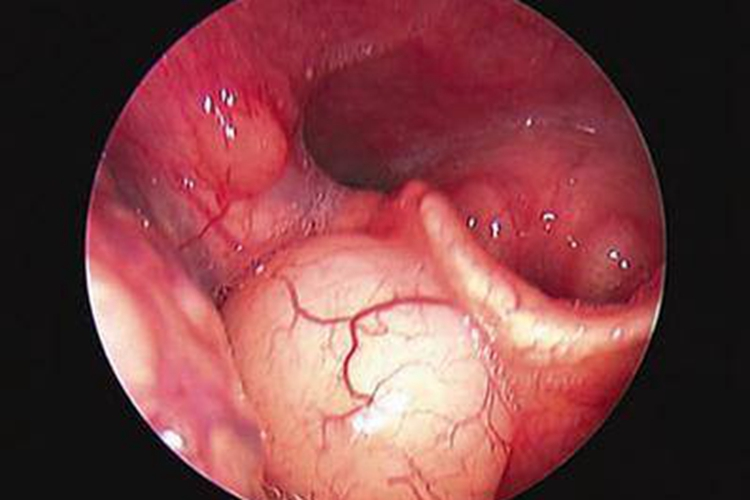

呼吸系统症状:杨梅过敏可表现为鼻痒、鼻充血、流鼻涕、喷嚏、咳嗽、声音嘶哑等,严重者会出现喉头水肿。